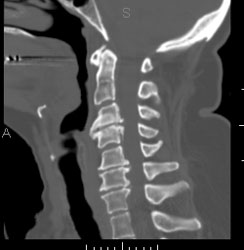

CT-Scan van de wervelzuil

Een ct-scan van de wervelzuil wordt in principe aangevraagd om letsels ter hoogte van de wervels te beoordelen, of om de doorgankelijkheid van het ruggenmergkanaal te controleren. Den hier aan het opsporen van een discus hernia, of een traumatisch letsel van een wervel.

Vraagt in principe geen specifieke voorbereiding.

De patiënt gaat op de rug liggen op de onderzoekstafel en moet blijven liggen tot na het onderzoek. Het is hier van belang dat de patiënt niet meer van positie verandert.

Contrast wordt hier in sommige gevallen toegediend, maar dit is geen regel.